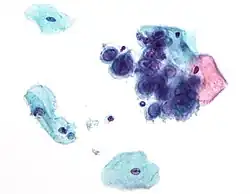

Chlamydia trachomatis bacteria found in a pap test of the cervix in a case of chlamydia | |